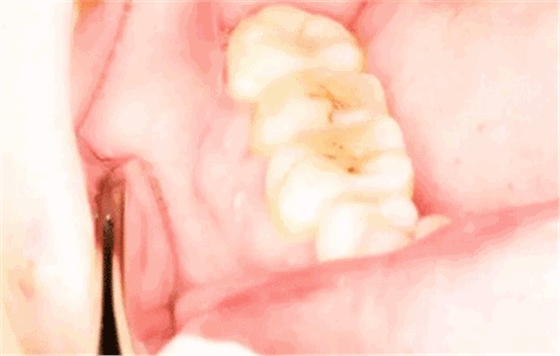

圖3.術(shù)前口內(nèi)影像情況:48頰側(cè)牙齦紅腫。照片有點(diǎn)曝光過度。不理想。